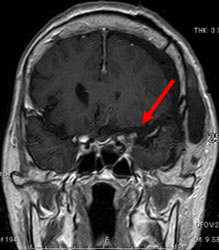

当院での症例をお示しします。症例は66才女性、進行する左眼の視力(左:手動弁)、視野障害にて当院来院。MRIにて赤矢印のように左蝶形骨内側に大きな腫瘍を認めます。開頭手術治療前に腫瘍の栄養血管にカテーテルを入れて、固体塞栓物質を造影剤と混ぜて注入します。最後に再開通しない様プラチナコイルを留置して終了します。その2日後に腫瘍摘出を行いましたが、出血は少量で輸血も行っておりません。視力も左は1.5まで改善し、患者さんは元気で退院しました。(図1-a・b、図2-a・b、図3-a・b、図4-a・b)

図3-a:術前 |

図3-b:術後 |